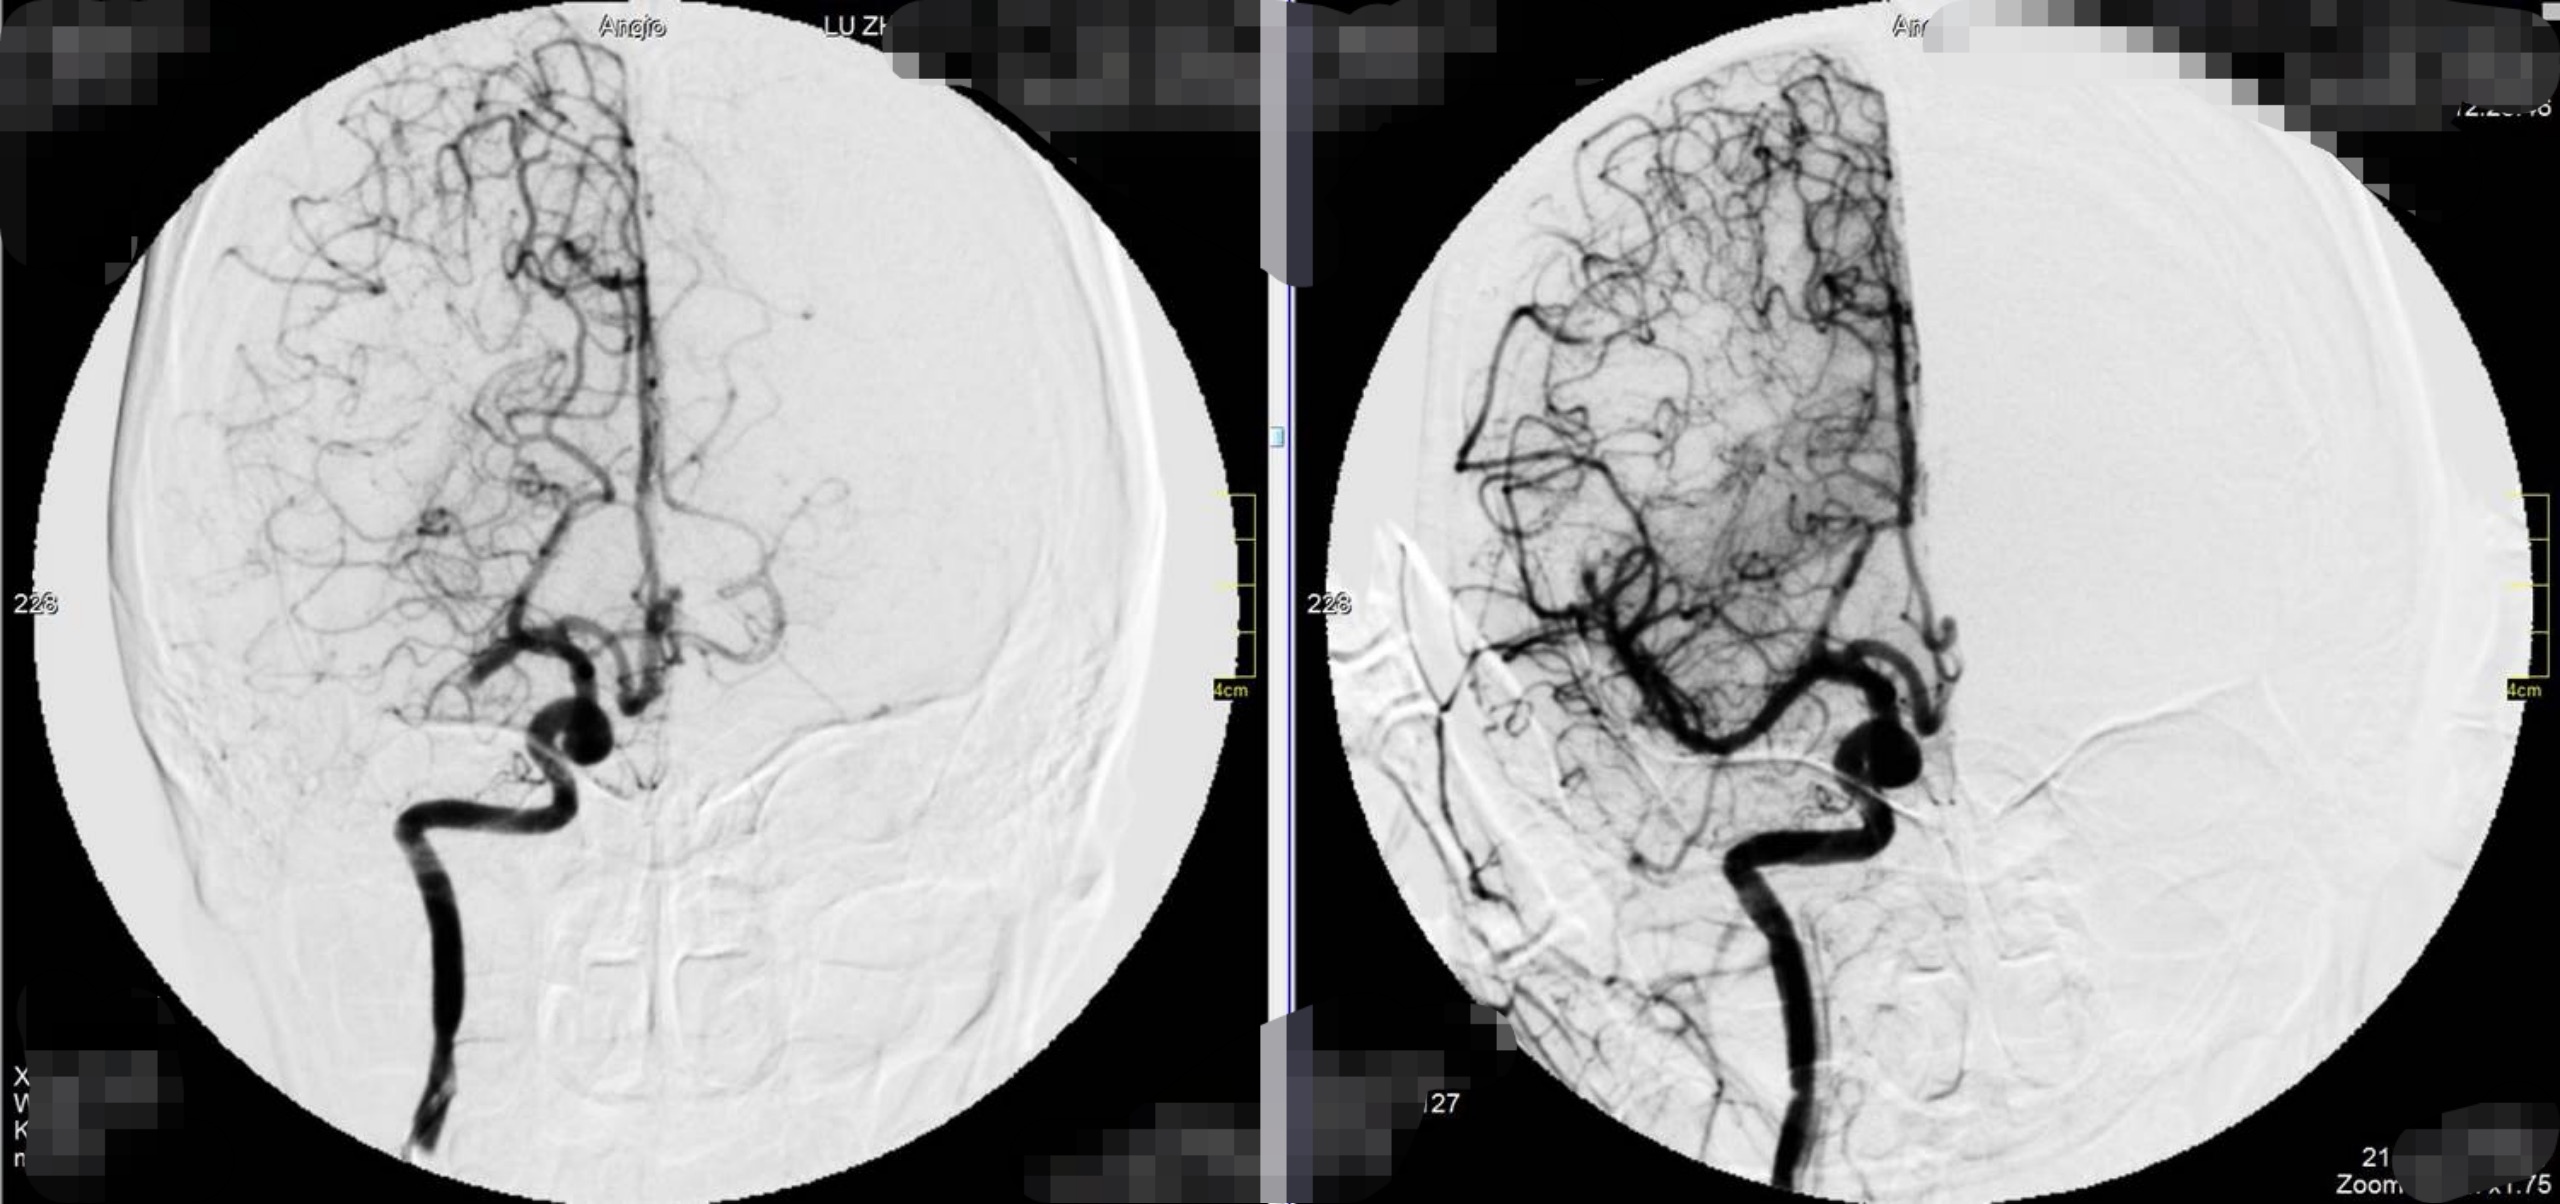

左图为术前,右图术后,对比看到血管成功开通